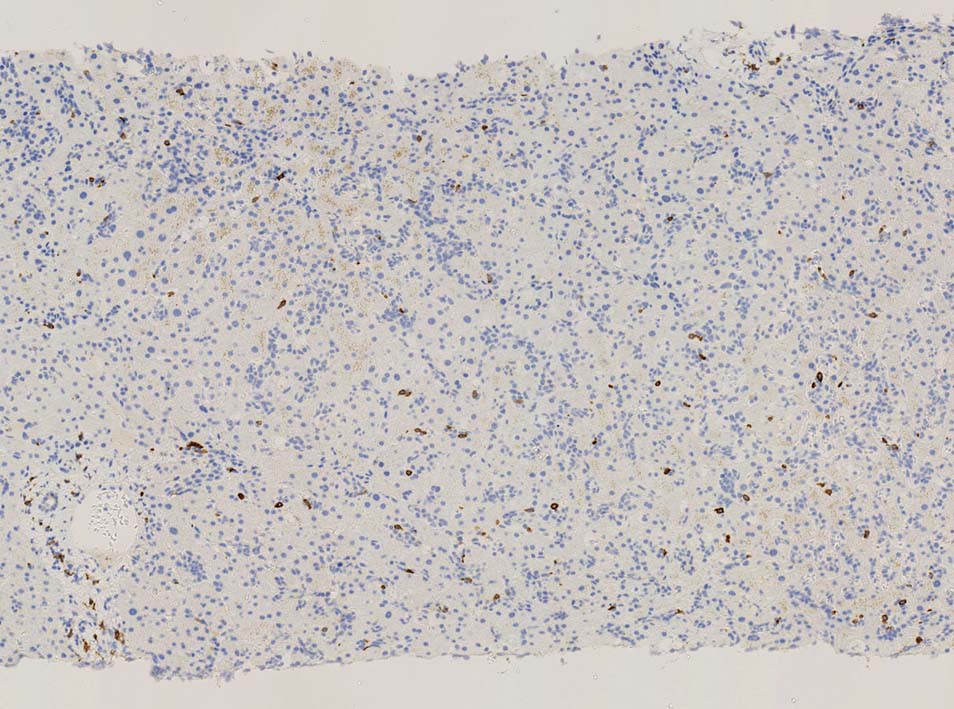

TIA1は陽性であるが, granzymeBは陰性細胞が多い.

ASD-GiemsaではASDに染まらない(陰性の)あやしい細胞塊があるように見える. 細胞小塊はCD3陽性.

骨髄クロットでは, 十分量が採取されているにもかかわらず, CD3陽性細胞は微小な集簇巣が2個ほど認められるのみであとは散在している.

免疫染色でCD3陽性となる細胞集塊のASD-Giemsa像. 肝類洞内浸潤細胞に比較して核, 細胞が紡錘形の傾向を示している.